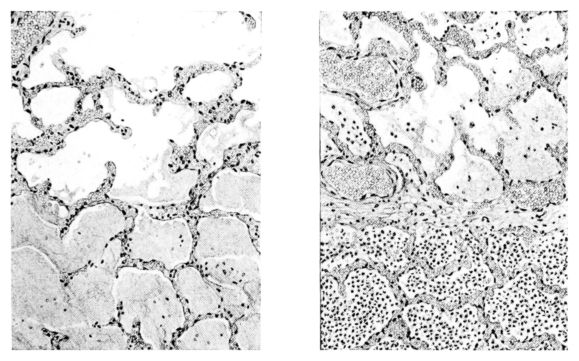

A more striking picture, however, even than this aplastic alveolar exudate appears in the terminal bronchioles. In many instances, these are conspicuous on account of their size, for they are dilated to form prominent, often irregular, sacs (Fig. XV). The distention of these terminal bronchioles may be so great that the surrounding alveoli are compressed. What makes them even more conspicuous is their lining, once epithelium, but now a swollen, thick, homogeneously staining material, with complete loss of architecture; the material forms (with hematoxylin and eosin) a red band limiting the lung tissue and sharply demarcating it from the exudate within the bronchioles (48, 92). However, this ribbon of red, often thickened by fibrin deposition, is not always pure, for bacteria thrive in the dead tissue. They occur singly, paired, in chains, and also as circumscribed, dense masses which in size and position, simulate nuclei (162) (Fig. XVI). This same hyalinization of the epithelium, it will be recalled, occurs in the larger bronchi (Fig. V), and there, too, bacteria frequently develop in the dead tissue (Fig. VIII). In the smallest bronchiolar ramifications, acute epithelial necrosis is not infrequently encountered, even when the surrounding lung tissue is relatively normal (Fig. XVI). That the process does not stop with the epithelium, but, as in the larger bronchi, may extend through the entire structure of the bronchioles, is manifest. Even the alveolar walls may be involved and frequently homogeneous pink or red bands, now the phantom of the former viable lung tissue, mark the presence of the old wall of the alveolus (Fig. XVII). Occasionally, some architecture remains in this pink ribbon and then the involvement seems to be primarily in the vessels of the wall. Not all the vessels are involved, and next to a hyaline thrombus in one, there may be fresh blood, usually red blood, in its neighbor. The alveolar epithelium is usually denuded and thus accentuates the intensity of the change.

Summary.

The diffuse involvement of all the lung tissue, chiefly with a serous exudate in the subpleural, interstitial, perivascular, and peribronchial tissues, as well as in the alveoli, is associated with other elements which occur in aplastic reactions; red blood cells, fibrin, and bacteria. Added to the aplastic exudate is an acute necrosis of bronchial and alveolar epithelium involving at times the walls of these structures; consequently, the histology of this disease is almost as specific as that of any biological reaction.